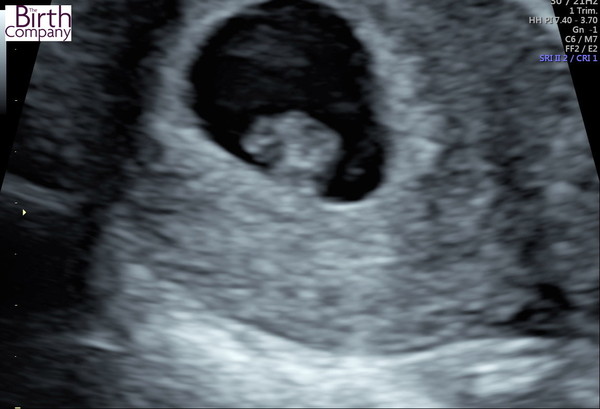

We had a scan yesterday and everything looking good with dates matching up, lovely strong heartbeat too! Here's a pic attached of the funny little blob.

Awe bearhuggy how cute. How many weeks are you

Thanks @twobambinos, I am 7+2 today...apparently babe is the size of a blueberry !!